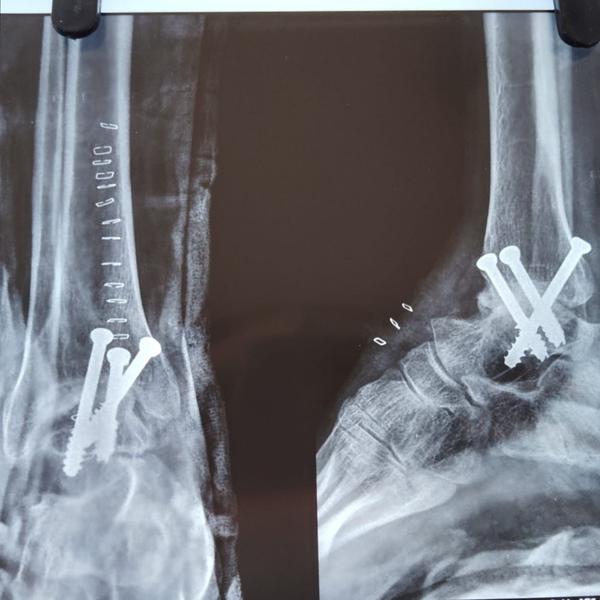

Ankle Arthrodesis

View DetailsSuccessful Hip fracture fixation surgery in Greater Noida/ Noida extension